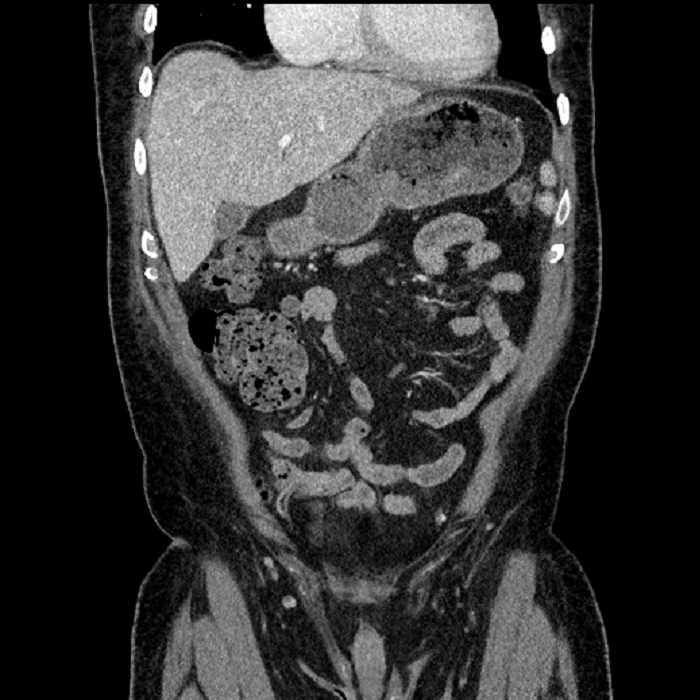

Age: 63

Sex: Male

Indication: Abdominal pain

• Large fluid density structure in hepatic segments 7 and 8 measuring 10 x 7 x 7 cm with internal septation and circumferential ill-defined low density compatible with edema

• Peripherally enhancing subcapsular collections along the anterior margin of the left hepatic lobe measuring 3 x 1 cm and 2 x 1 cm

• Clearly marginated fluid density structure in segment 7 and several other scattered tiny hypodensities, which likely represent cysts

• Hepatic abscess

Acute sigmoid diverticulitis complicated by a small contained perforation and a large abscess in the right hepatic lobe. Additional small subcapsular abscesses along the anterior margin of the left hepatic lobe.

• The classic CT imaging appearance is a double target sign with internal low density surrounded by an internal enhancing rim (capsule) and a low density external rim (edema)

• Abscesses may be unilocular or multilocular

• Gas is present in a minority of cases

Hepatic abscess showing the double target sign with low density internally surrounded by a thin inner enhancing rim (red arrow) and ill-defined outer low density rim (yellow arrow). Blue arrow indicates an internal septation. Red arrows: additional smaller subcapsular abscesses. Red arrow: focal contained perforation associated with diverticulitis.